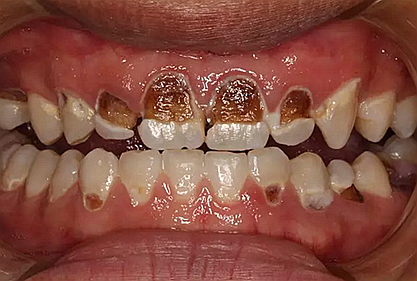

我們的主人今年才25歲,可卻從很小的時候就嗜好喝可樂等碳酸飲料,幾年下來,讓我們兄弟姐妹們整天浸在碳酸里受這蝕骨之痛,原本皎潔的外貌如今早己經(jīng)是腐蝕不堪、丑陋無比,更有甚者,一些兄弟姐妹們已經(jīng)病入膏肓,被病痛折磨奄奄一息。

下面是醫(yī)生眼中和ct下的我們

一身病痛啊

牙結(jié)石、牙齦炎癥、牙體殘缺、慢性牙髓炎、蛀牙......